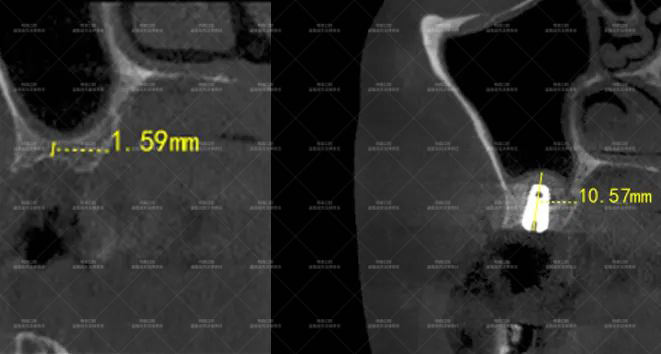

口腔CT片更直观地暴露了问题:支撑牙齿的骨头(牙槽骨)几乎被“啃”掉了三分之二,最薄的地方仅1.59mm......

患者术前牙槽骨最“薄”处仅1.59mm

时间来到了2025年5月,但CT片显示倪女士16号牙的骨量只有1.59mm太少了,这远远还达不到做种植牙的条件!

如今,倪女士的种植体已经开始和骨头长在一起,16号牙的骨量从1.59mm增长到10.57mm,再过几个月就能装上牙冠。

术前术后ct对比:牙槽骨从1.59mm增厚至10.57mm